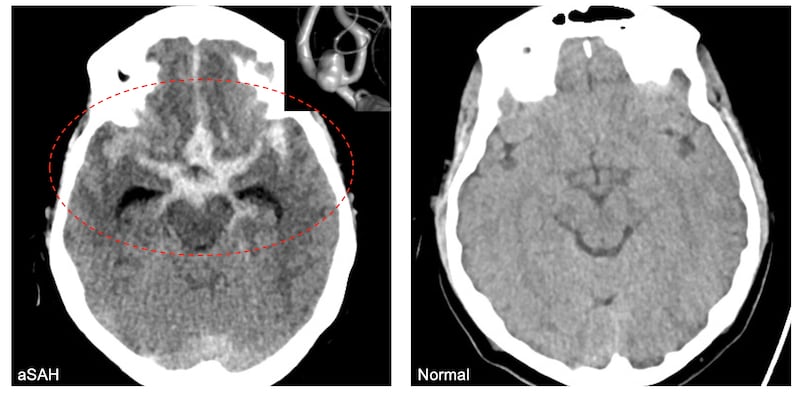

New research from University of Utah Health has for the first time linked the small particulate matter pollution to ruptured brain aneurysm, which is more formally called aneurysmal subarachnoid hemorrhage. The resulting brain tissue damage can be severe enough to leave patients paralyzed or in a coma, if they survive it.

That type of brain bleed kills about a third of the time, while a like share suffer very severe neurologic injuries," per Rennert.